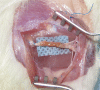

Figure 1

Figure 1. Harvesting a small intestine segment (a). Bridging the sciatic nerve gap with intestinal conduit and entabulating the proximal and distal stumps (b).